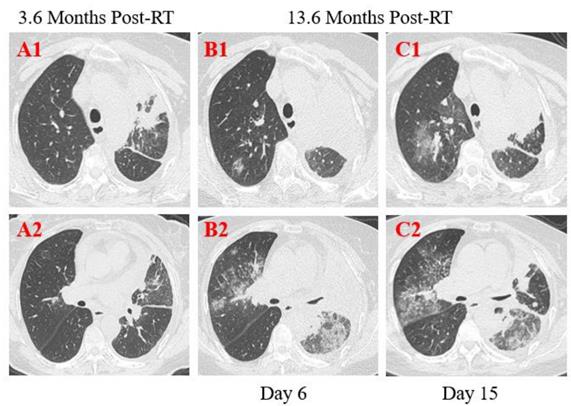

Figure 3

Transverse thin-section serial CT scans from a 55-year-old female with suspected COVID-19 pneumonia. Chest CT images performed on the 6th day after symptom onset indicated an enlarged mass with calcification in the left upper lobe and lung hilum and multiple mediastinal lymph node metastases (A1, B1, C1), bilateral diffused ground-glass opacities with partial consolidation (B2). Follow-up CT on the 15th day demonstrated continuous development in the scope and extent of lung lesions (C1, C2).

Patient 2: A 55-year-old female was diagnosed with left lung adenocarcinoma with intrapulmonary metastases and multiple bone metastases staged with T4N3M1 and received palliative comprehensive treatment based on target therapy of epidermal growth factor receptor (EGFR) inhibitor in April 2018. She was admitted to the hospital on January 23, 2020, with dyspnea for 1 week and exacerbation for 1 day after more than 1-year targeted therapy. Fatigue, chest distress, and sputum production with cough were also presented in this patient. She had no fever, was not from the infected area, and did not contact with infected persons. The physical examination revealed disappeared breath sounds of the left lung during auscultation, and laboratory studies showed slightly elevated white blood cell and neutrophil, but no changes in lymphopenia. Elevated concentrations of D-dimer, CRP and NT-BNP were displayed at admission. Sputum culture examination revealed normal flora growth without Hemophilus influenza or fungal growth. Furthermore, compared with the previous CT scans 10 months ago, chest CT images performed on the 6th day after symptom onset showed enlarged mass with calcification in the left upper lobe and lung hilum with the maximum section of about 79 mm*48mm, and multiple mediastinal lymph node metastases. The boundary between the left upper lobe and lung hilum is obscure with atelectasis. Magnified irregular nodules scattered in both lungs, and metastatic tumors of the left pleura, the left pleural effusion and pericardial effusion increased in the extent and quantity (Figure 3. A1, B1, C1). There were bilateral diffused ground-glass opacities with partial consolidation (Figure 3. B2), and a reticular pattern associated with bronchiectasis and intralobular or interlobular septal thickening (Figure 3. B2), indicating the possibility of viral pneumonia. After 9 days of anti-infective therapy with tazocin, combined with aggressive supportive care and glucocorticoid therapy (methylprednisolone), follow-up CT demonstrated continuous development in the scope and extent of lung lesions (Figure 3. C1, C2). Repeated two times of swab nucleic acid tests for the COVID-19 were negative, and blood high throughput screening for pathogenic microorganisms or viruses was also negative. The patient’s disease continued to progress and she died on February 6, 2020 in the Department of Oncology.